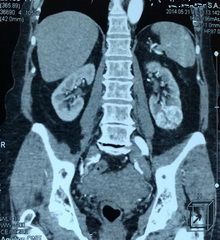

Рис. №2. Мультиспиральная компьютерная томография органов мочевой системы с контрастированием. Опухоль нижнего сегмента левой почки до 5 см, активно накапливающая контрастное вещество.

Пациентке выполнена лапароскопическая резекция левой почки.

Гистологическое заключение: почечно-клеточный рак, светлоклеточный вариант.